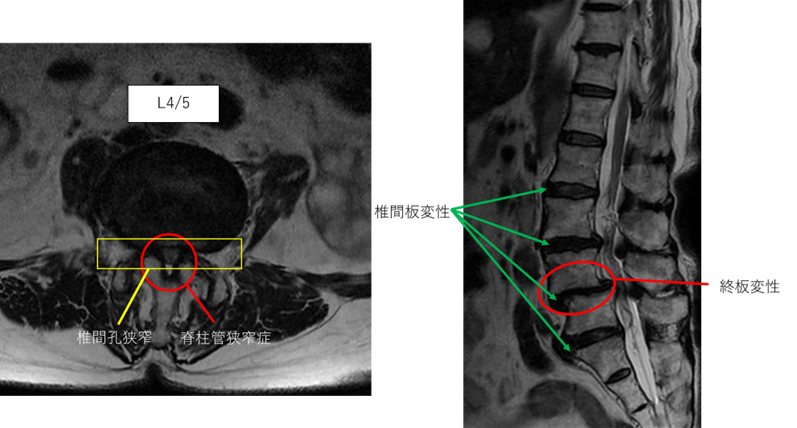

L1/2: 異常なし

L2/3: 椎間板変性症

L3/4: 脊柱管狭窄症、椎間板変性症、椎間孔狭窄

L4/5: 脊柱管狭窄症、椎間板変性症、椎間孔狭窄、終板変性

L5/S: 椎間板変性症、椎間孔狭窄

以上の事が画像上認められます。

L3/4、4/5、5/sに

脊柱管狭窄症、椎間板変性症、椎間孔狭窄、終板変性 を認め、主症状の原因の可能性が高い。